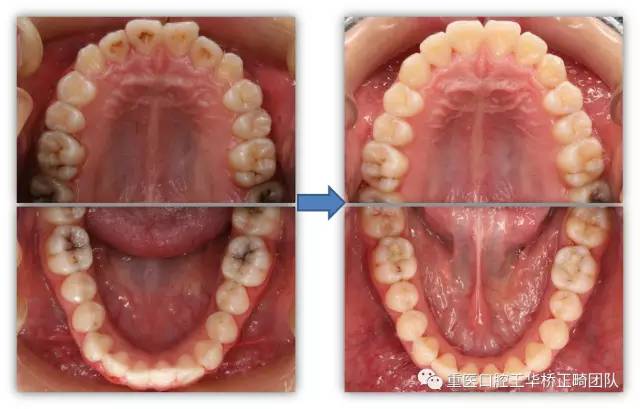

请一起来看一下矫正前后的对比吧

矫正前后牙齿对比